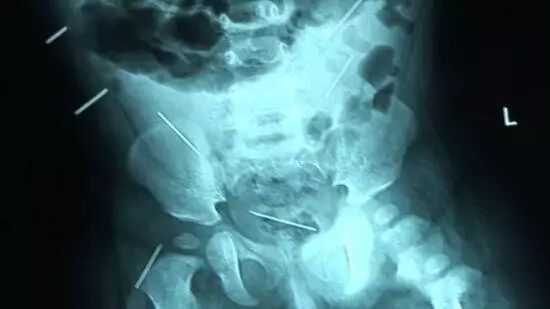

2014年,山东聊城。一个年仅11个月大的女婴体内被扎入12根钢针,从臀部、腹腔到骨盆。

经过警方调查,扎针人系女孩的家人,因为迷信“在女孩身上扎针下胎生男孩”。